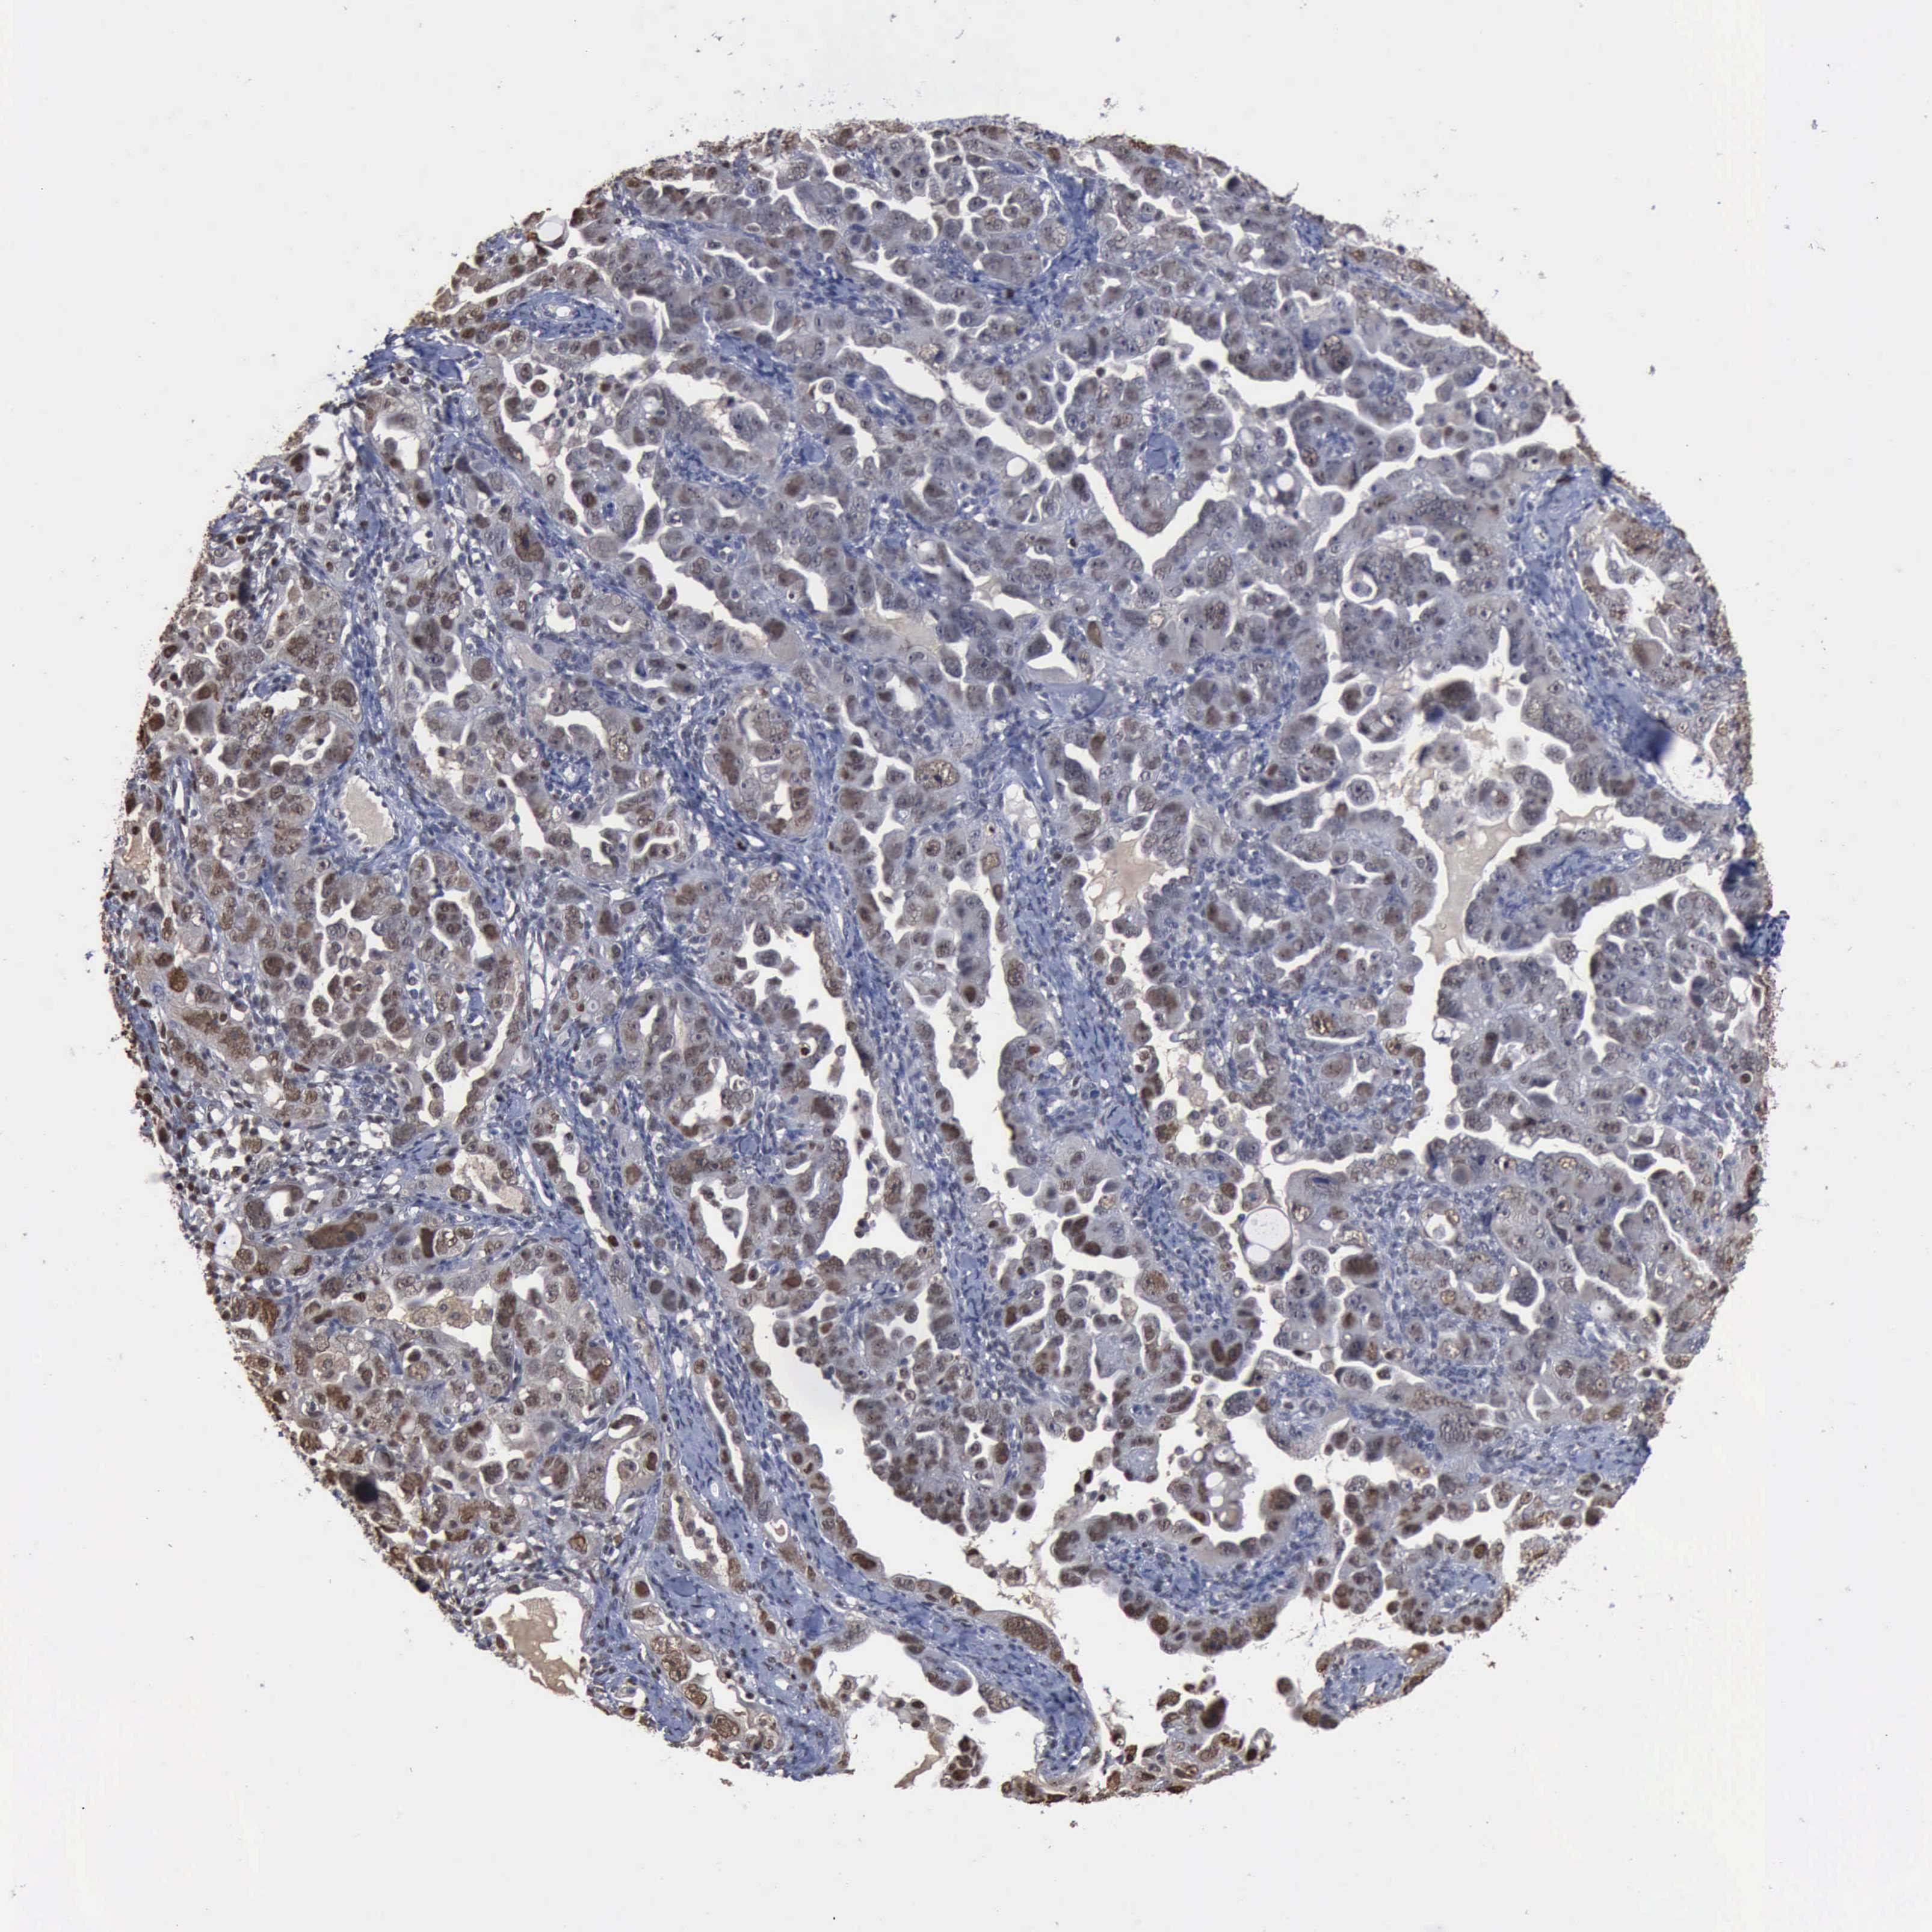

OVARIAN CANCER - Protein expressioni

A mouse-over function shows sample information and annotation data. Click on an image to view it in a full screen mode. Samples can be filtered based on level of antibody staining by selecting one or several of the following categories: high, medium, low and not detected. The assay and annotation is described here.

Note that samples used for immunohistochemistry by the Human Protein Atlas do not correspond to samples in the TCGA dataset.

Antibody stainingi

Antibody staining in the annotated cell types in the current human tissue is reported as not detected, low, medium, or high, based on conventional immunohistochemistry profiling in selected tissues. This score is based on the combination of the staining intensity and fraction of stained cells.

Each image is clickable and will lead to virtual microscopy that enables deeper exploration of all samples and also displays staining intensity scores, fraction scores and subcellular localization as well as patient and tissue information for each sample.

HPA030521

Cystadenocarcinoma, serous, NOS

Carcinoma, endometroid

Cystadenocarcinoma, mucinous, NOS

Carcinoma, NOS